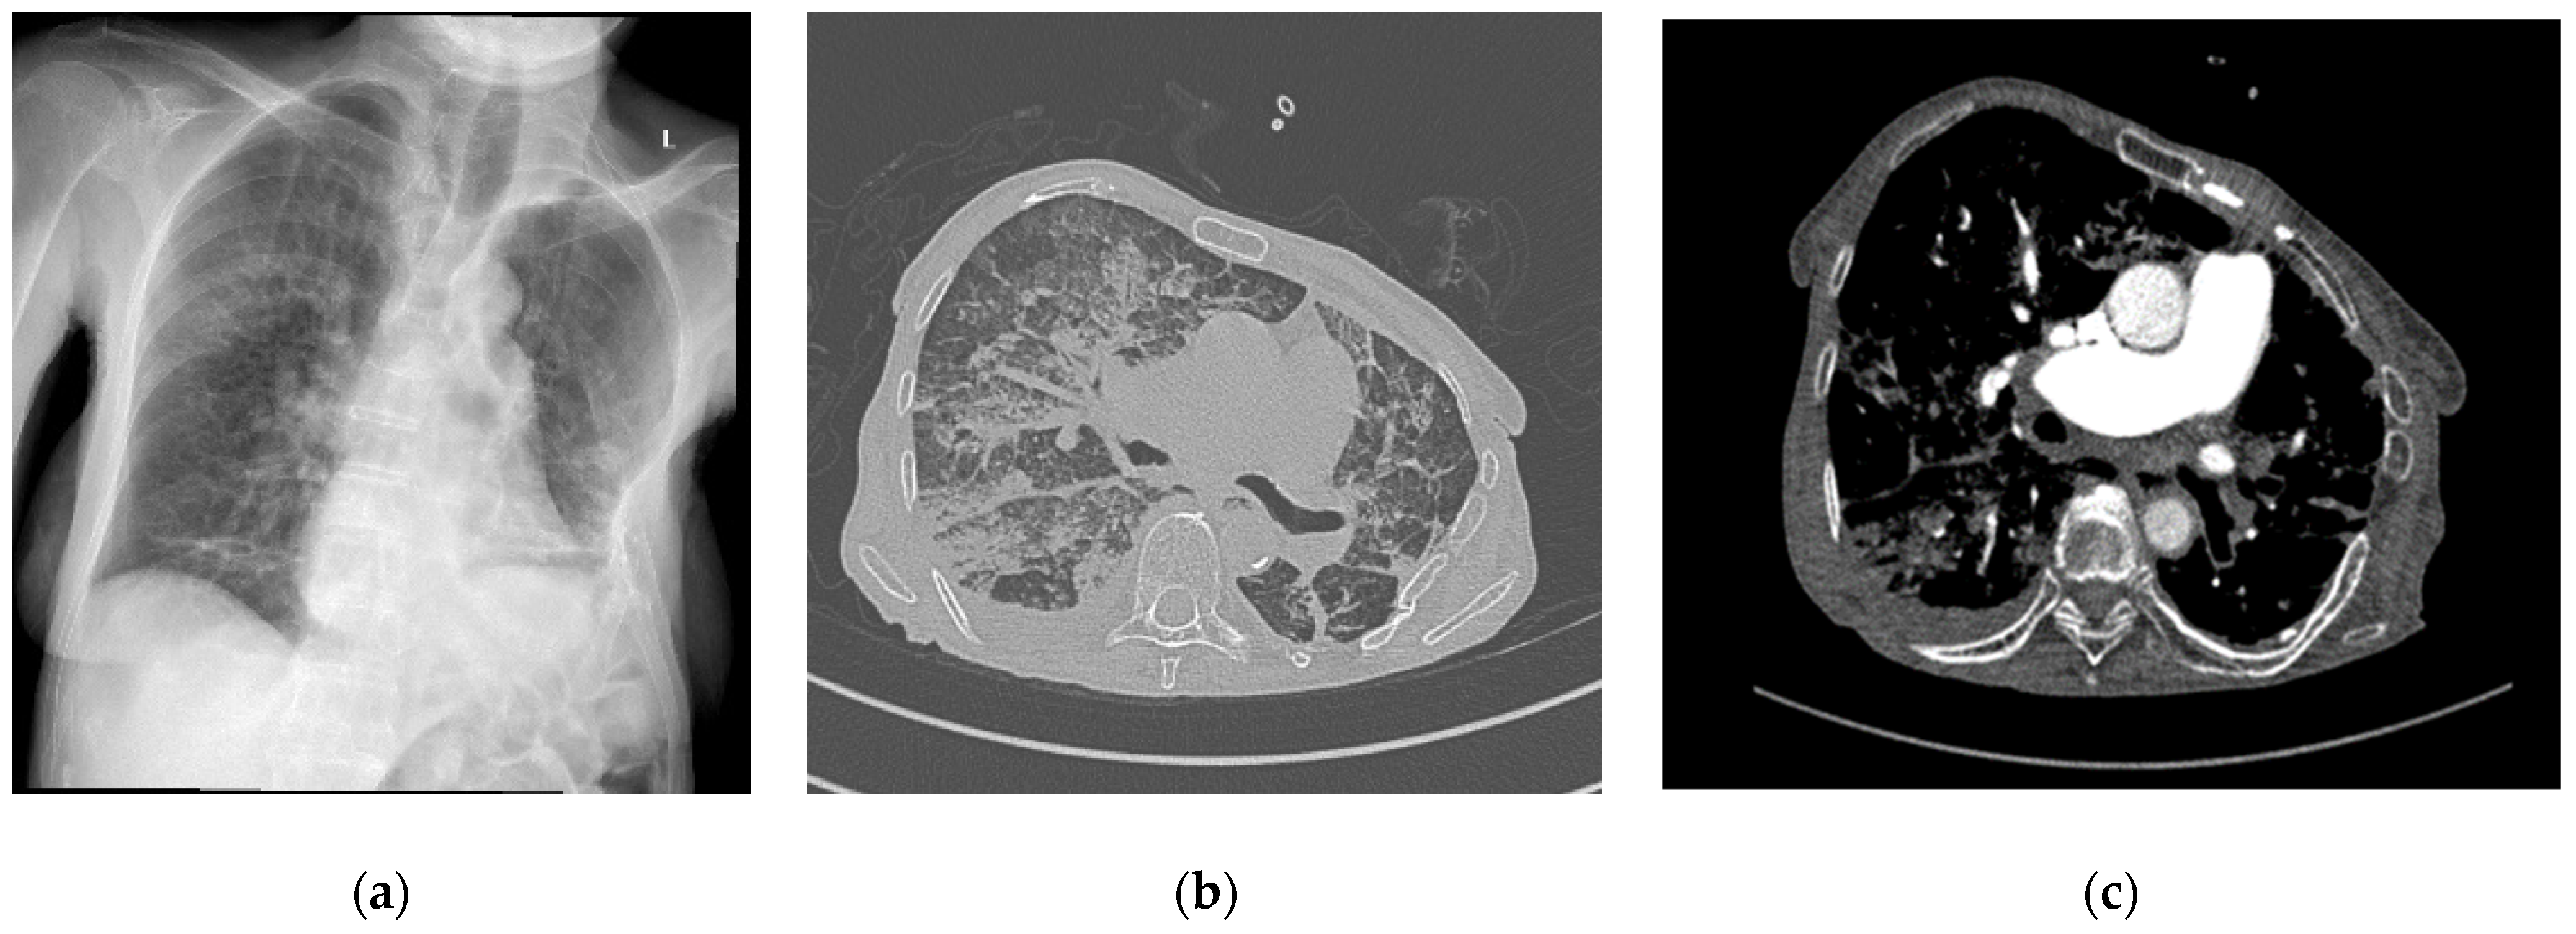

A 70-year-old female patient with right femoral neck fracture (FNF) garden type III returned to hospital after she refused surgical treatment 6 days ago. She was also suffering from pulmonary fibrosis (Figure 2a), rheumatoid arthritis (RA), chronic venous insufficiency (CVI), and high blood pressure (HBP) stage 1.

Figure 2.

(a) Chest X-ray at admission; (b) contrast-enhanced chest CT scan lung window after surgery; (c) contrast-enhanced chest CT scan soft tissue window after surgery. L—left side.

The same day, a cemented total hip arthroplasty was performed under intraspinal regional anesthesia with 10 mg of 0.5% heavy (H) marcaine and 5 µg of sufentanyl. While the cement was digitally applied into the femoral canal, the patient presented an emetic episode and tachycardia arrhythmia. After the surgery, she was agitated and desaturated. CT angiography (CTA) was requested that excluded pulmonary embolism (PE), describing bilateral bronchopneumonia outbreaks, pulmonary fibrosis associated with bronchiectasis, and pulmonary hypertension, with minimal pleurisy (Figure 2b,c).